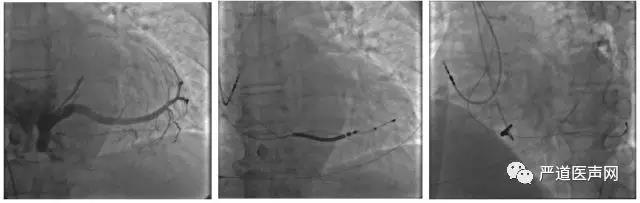

手术过程:

行冠状静脉造影后选择侧静脉为靶血管,经腋经脉植入电极导线,心房电极植入右心房心耳,右心室电极植入中低位室间隔,左室电极植入冠状静脉侧分支,术中测试左心室阈值2.5V,感知15mV,阻抗680Ω;右心室 阈值0.75V,感知20mV,阻抗580Ω。出院后心电图显示QRS波时限138ms。 CareLink远程随访显示患者动态BIV起搏比例99%,AV间期一直动态优化,术后5个月心脏超声提示EF 52%,几乎与正常人相同。5个月后患者回医院随访,自述目前心功能明显改善,可以正常生活,饮食睡眠良好,期间没有因为心衰再住院治疗。

分别为:造影、AP、LAO45°

术者总结:

AdaptivCRT可以通过患者活动度和传导情况自动优化起搏间期。